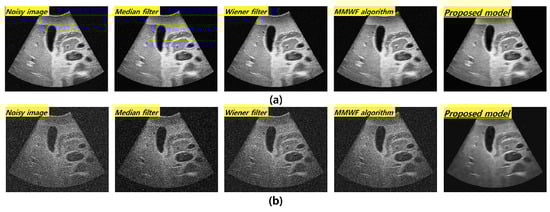

Evaluation of Denoising Performance of ResNet Deep Learning Model for Ultrasound Images Corresponding to Two Frequency Parameters

3. Results